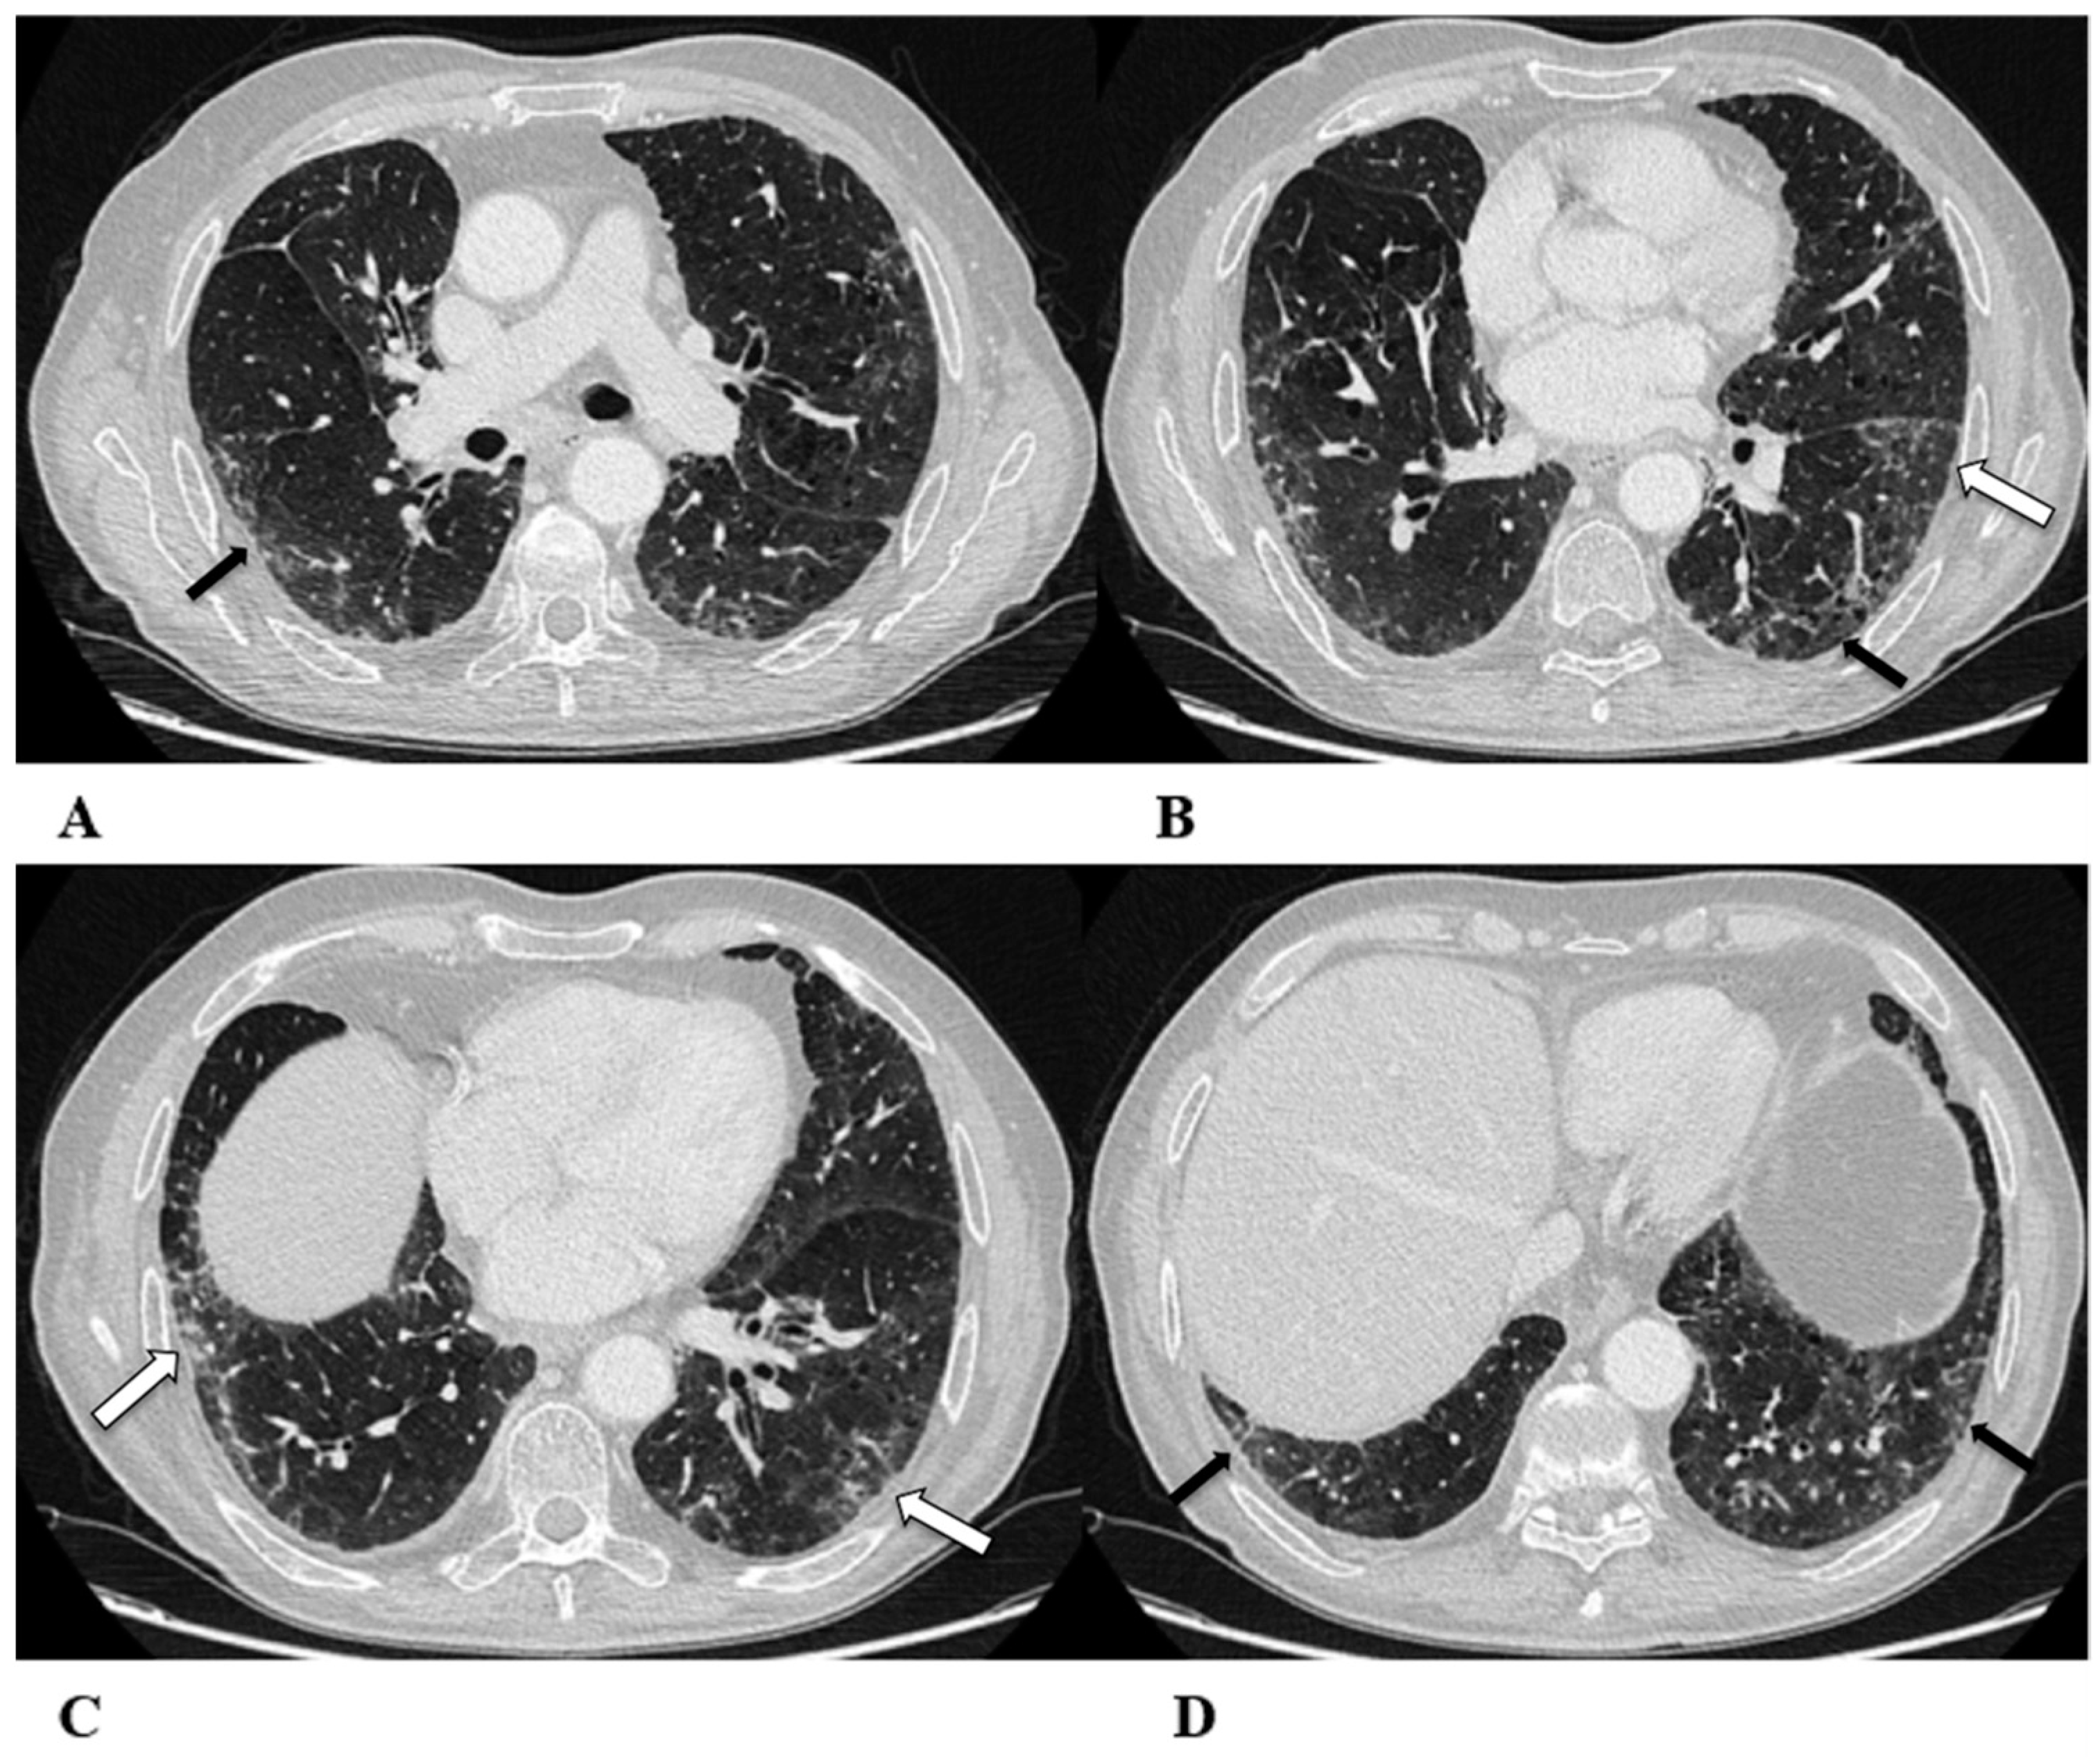

Non-specific interstitial pneumonia (NSIP). Non-specific interstitial pneumonia represents the second most commonly described pattern of ICI-related pneumonitis. It is defined pathologically by different degrees of interstitial inflammatory cell infiltrates and/or fibrosis. HRCT characteristics in patients with NSIP consist of GGOs associated with irregular reticulations and traction bronchiectasis/bronchiolectasis. Honeycombing is infrequent and minimally represented. NSIP distribution is usually bilateral and symmetric, predominantly subpleural and basal, and often with sparing of the immediate subpleural lung.

The NSIP pattern should be distinguished from atypical pneumonia based on clinical analysis. The greater involvement of the lung bases and recurrent relative subpleural sparing must be considered in the clinical assessment of the patient, as they are uncommon findings in infectious processes. It is also necessary to exclude the concomitance of immune disorders and connective tissue diseases [9,12].

(A–D) A 70-year-old man with lung adenocarcinoma and brain metastases treated with pembrolizumab, carboplatin and pemetrexed as first-line treatment. Two months later, the patient had dyspnea and dry cough, without fever.

Axial chest CT scans show mild subpleural reticulation in the lower lobes (black arrows (A,B,D)) and patchy bilateral and partially confluent areas of GGO in both lungs predominant in the lower lobes (white arrows (B,C)). Incidental findings: rare small lucent areas of centrilobular emphysema, especially in both upper lobes.